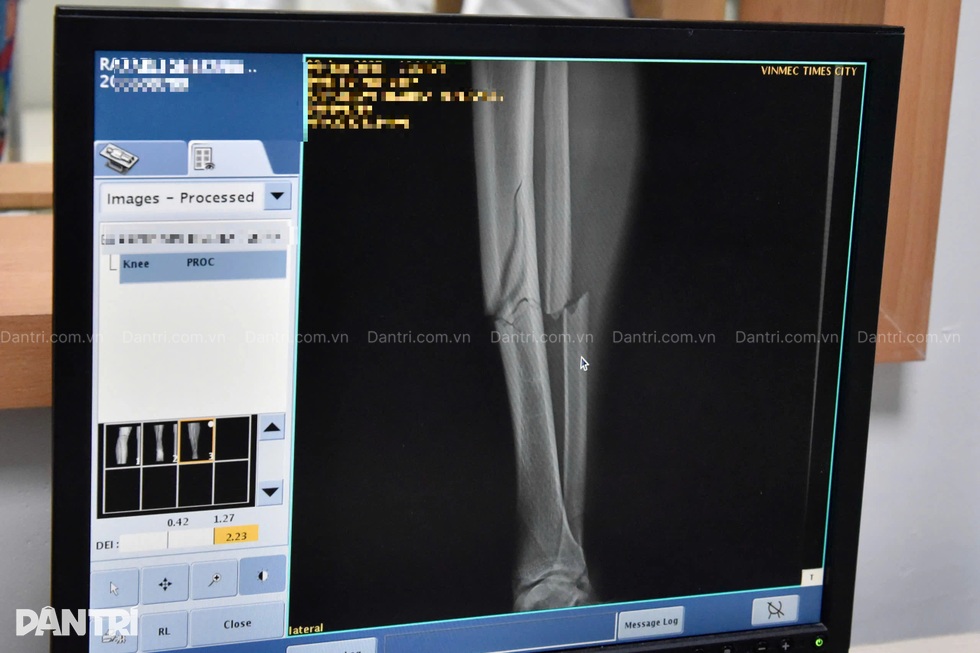

Sau ca mổ "giải cứu" chân phải bị tổn thương phức tạp của Xuân Son trong đêm 6/1, GS.TS.BS Trần Trung Dũng, Giám đốc Trung tâm chấn thương chỉnh hình và y học thể thao, Bệnh viện ĐKQT Vinmec Times City đã có những chia sẻ về tình trạng của Xuân Son cũng như đưa ra nhận định về khả năng phục hồi của cầu thủ này.

Quá trình phẫu thuật của Xuân Son diễn ra như thế nào? Những thách thức lớn nhất trong việc điều trị cho Son là gì, thưa giáo sư?

- Ca này là phẫu thuật về xương, về kỹ thuật không quá khó, quá phức tạp, đòi hỏi công nghệ cao siêu, nhưng cần bác sĩ có kinh nghiệm, vừa là yêu cầu rất cao của một vận động viên chuyên nghiệp.

- Phẫu thuật cho Xuân Son được thực hiện ngay trong vòng 24 giờ sau chấn thương và đã thành công tốt đẹp. Hiện Son đã có thể tự đi nạng trong phòng, sau 2-3 ngày tới là bắt đầu tập luyện phục hồi, với thời gian 6-8 tiếng/ngày.

Bên cạnh xương gãy, chúng tôi cần phải theo dõi sát hàng ngày nguy cơ đụng dập cơ tiến triển và nguy cơ thuyên tắc mạch của Xuân Son. Bên cạnh theo dõi lâm sàng chúng tôi cần xét nghiệm men cơ hàng ngày, siêu âm doppler hàng ngày để phát hiện các vấn đề sớm nhất và xử lý ngay.